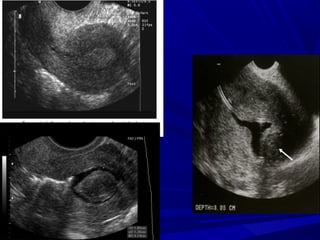

Saline infusion sonography

Sonohysterography

TVS may miss small polyps

Difficult to distinguish from thickened

endometrium

SHG helps in

accurate diagnosis

normal cavity